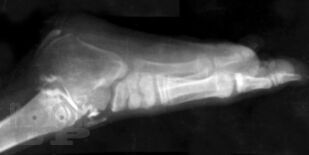

В монографии излагаются результаты многолетнихисследований, проведенныхв научно-исследовательском детском ортопедическом институте им. Г. И. Турнера. Рассматриваются вопросы клиники, диагностики и лечения врожденныхпороков развития костей голени у детей в возрасте от 3 мес. до 15 лет и старше. Описываются новые методики операций, основанные на сберегательной тактике, адекватные различным вариантам порока, позволяющие восстановить форму и функции конечности, техразновидностей порока развития костей голени, которые до настоящего времени считались неоперабельными и подлежали только ампутации. Монография предназначена для ортопедов, травматологов и хирургов.